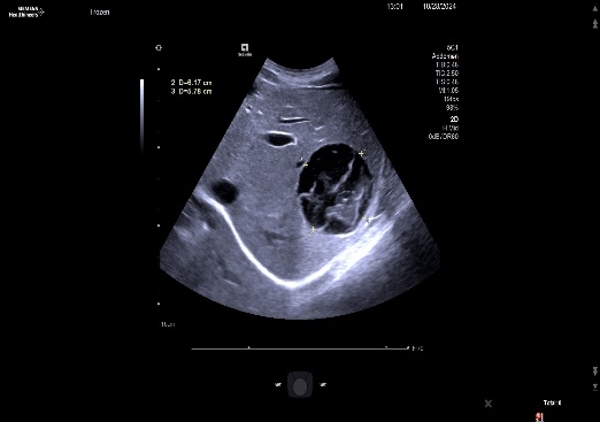

近期阿里地区人民医院收治一名28岁女性患者,体重40Kg,身高140cm,BMI20。以“体检发现肝包虫5年,肝区疼痛1年”之主诉入院。入院后完善B超及上腹部增强CT:肝脏S3段见大小8×7cm囊性病灶,S6、7段见大小约9×8cm 囊性病灶,诊断肝囊型包虫病(CE₃型)。我院援藏队员张立、何鑫、李洪亮及蔡艳组织MDT讨论,制定手术计划,考虑到患者年轻,肝脏体积小,药物作用慢,为防止包虫复发,及术后胆漏合并感染问题,决定采用外囊完整切除的根治性治疗。